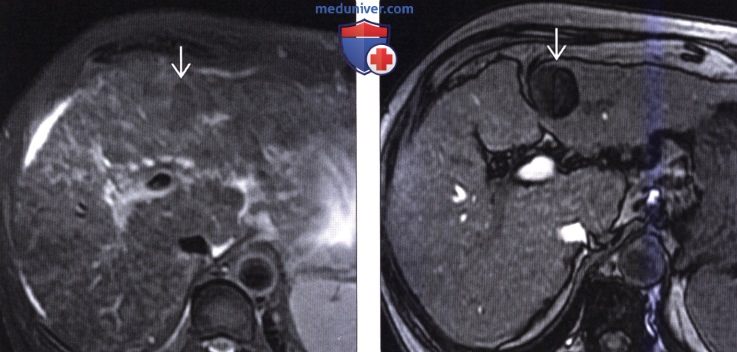

Методы динамического контрастирования печени на МРТ

Раздел: Снимки-подсказки